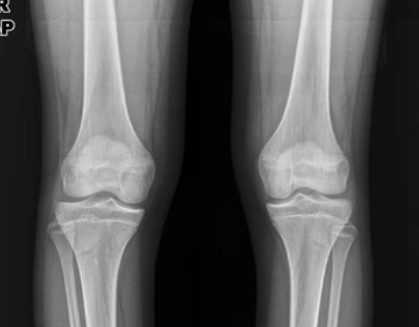

1. X선 검사 (X-ray): 일반적으로 성장판을 검사하는 방법으로 손목의 X선 사진을 찍어 성장판의 상태를 평가하는 방법입니다. 손목 관절 부위의 성장판이 어떻게 닫혔는지 확인하여 성장 가능성을 판단할 수 있습니다.